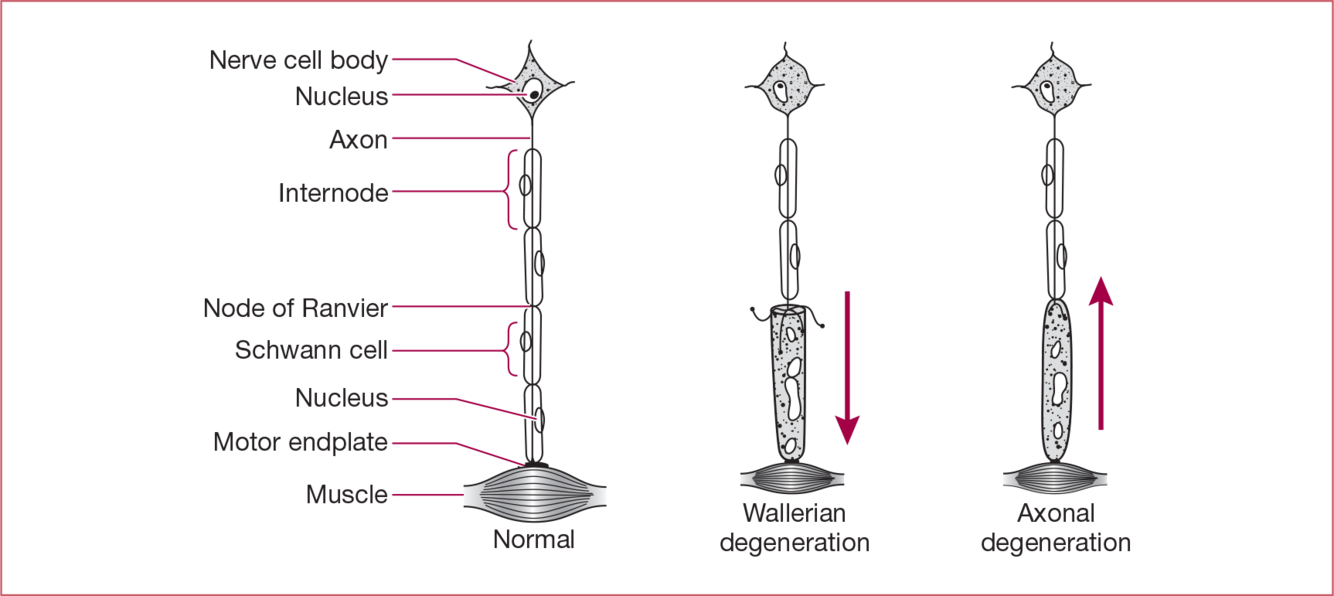

How does axonal degeneration differ from Wallerian degeneration?

Axonal degeneration starts distally and ascends whereas with Wallerian the nerve degenerates distally from the site of the lesion.

How long does it take axons to regrow if connective tissue remains intact?

1mm/day or 1 inch/month